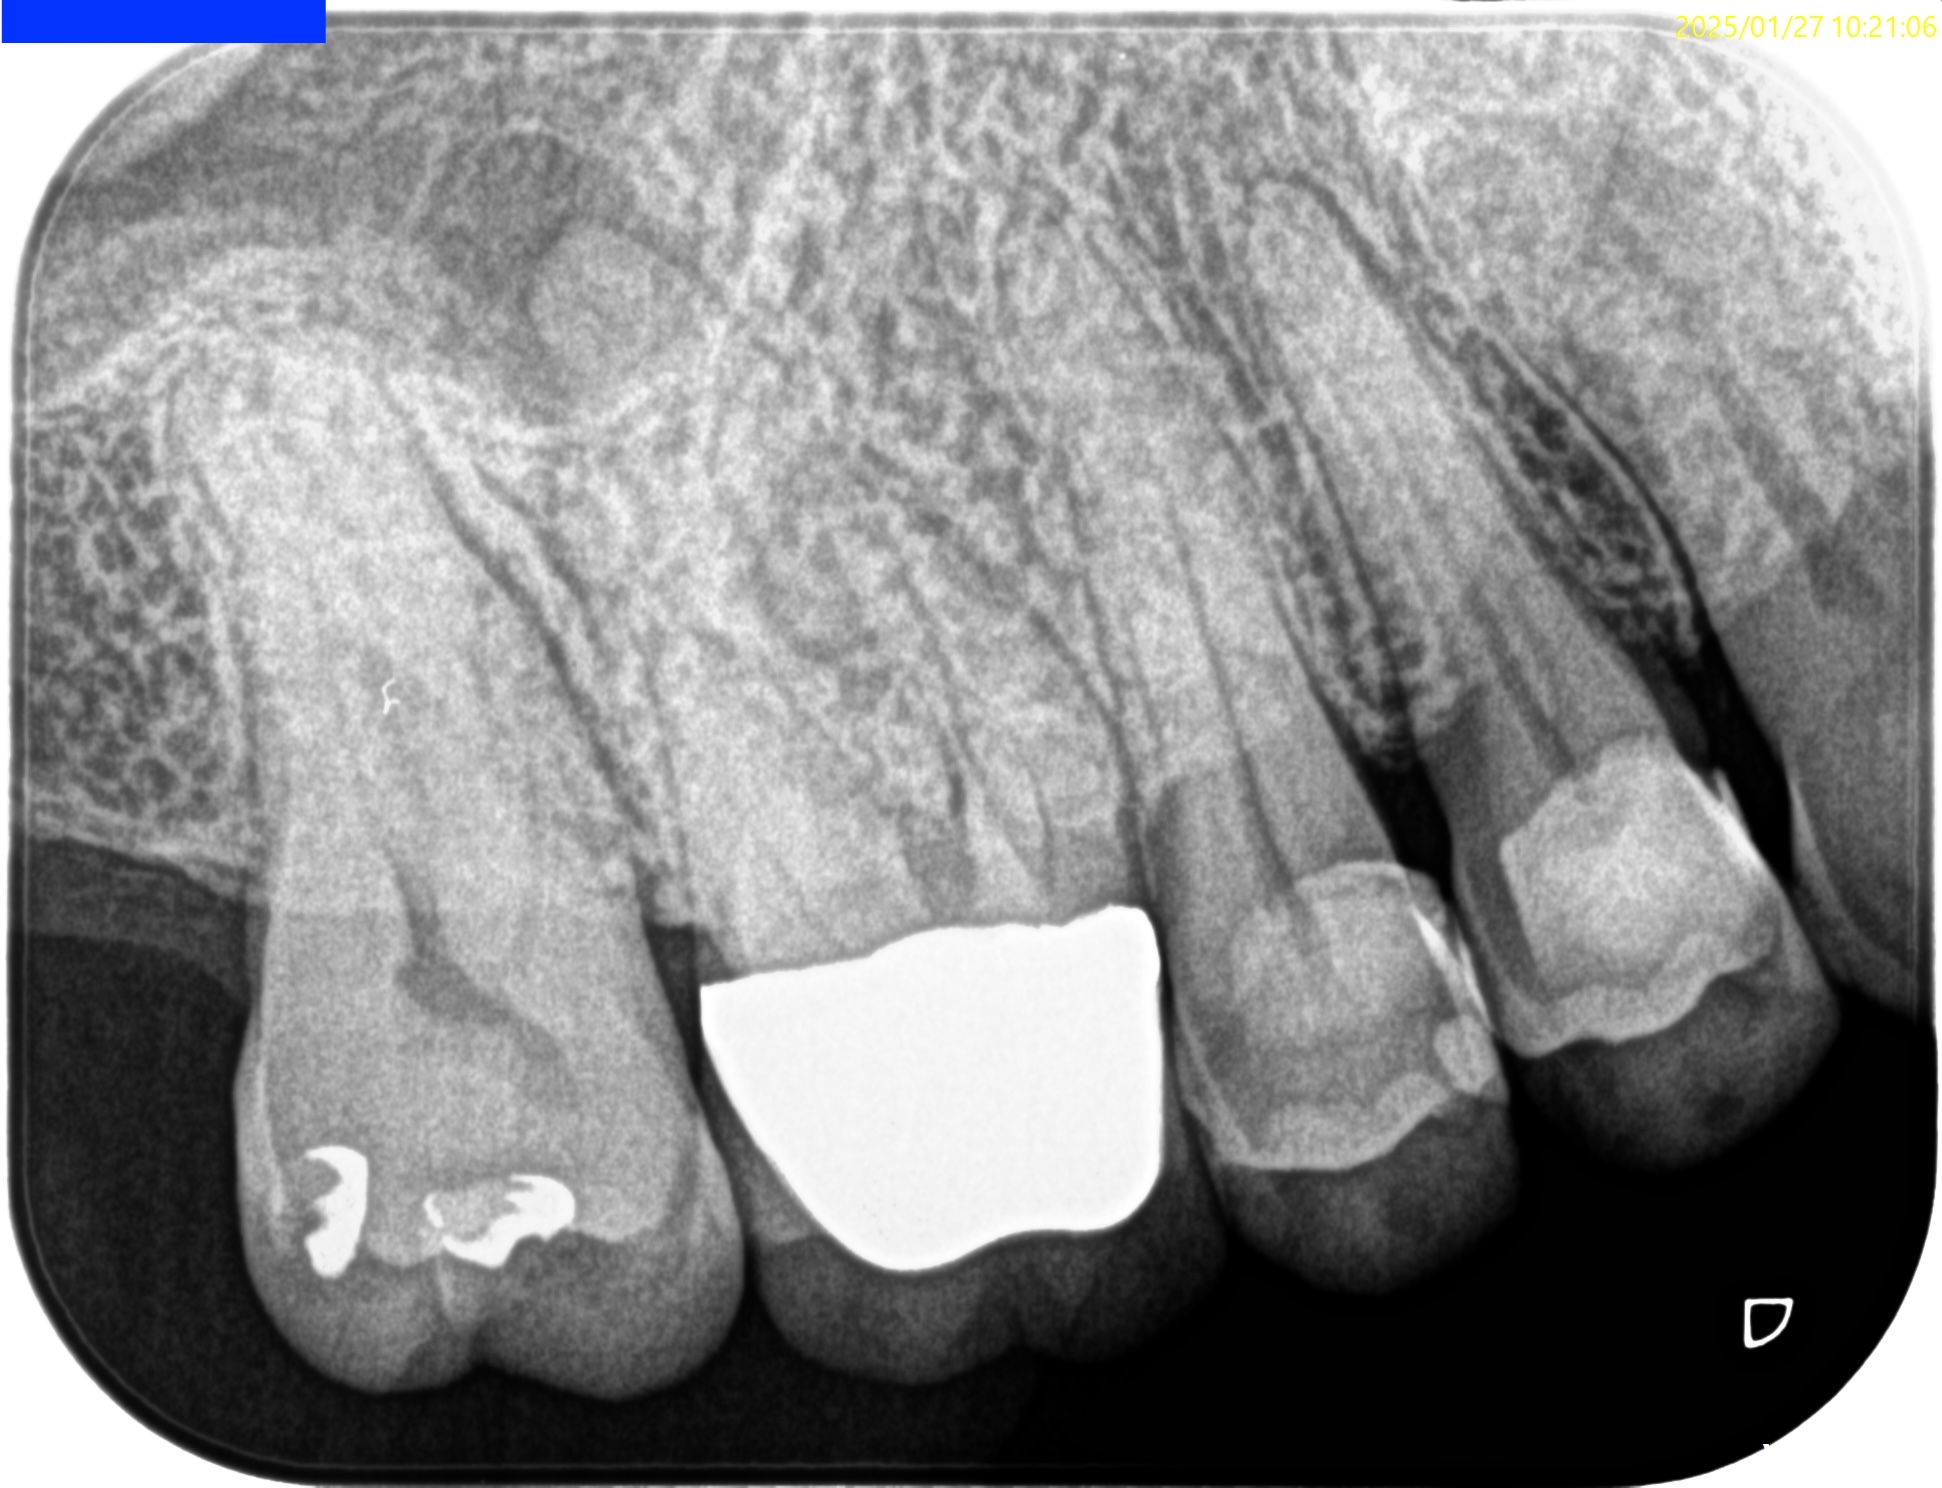

Pre-op Endo test(2025.1.27)

MB,DBのApexが歯槽骨から透けて見えている。

圧痛の原因はこれだ。

そしてSinus tract。

Pulp Dx: Pulp Necrosis

Periapical Dx: Chronic apical abscess

Recommended Tx: RCT